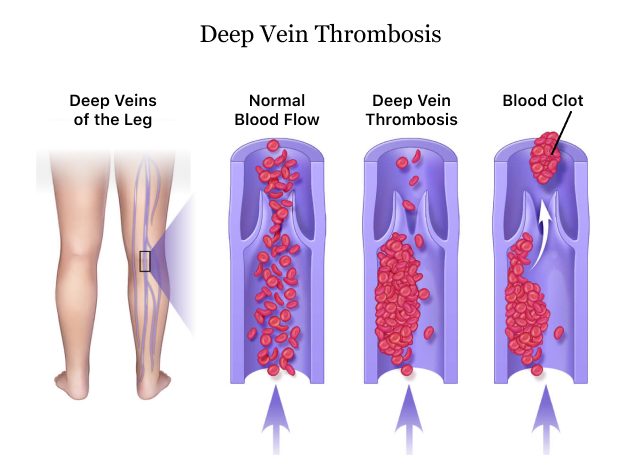

vein thrombosis deep venous thromboembolism treatment prevention femoral common thrombus distal proximal knee ppt secondary powerpoint presentation

deep vein veins thrombosis leg

vein thrombosis dvt pathophysiology limb rcemlearning rarely typically occur

Deep vein thrombosis. Vein thrombosis dvt pathophysiology limb rcemlearning rarely typically occur. Venous anatomy thrombosis superficial veins deep health sources trusted